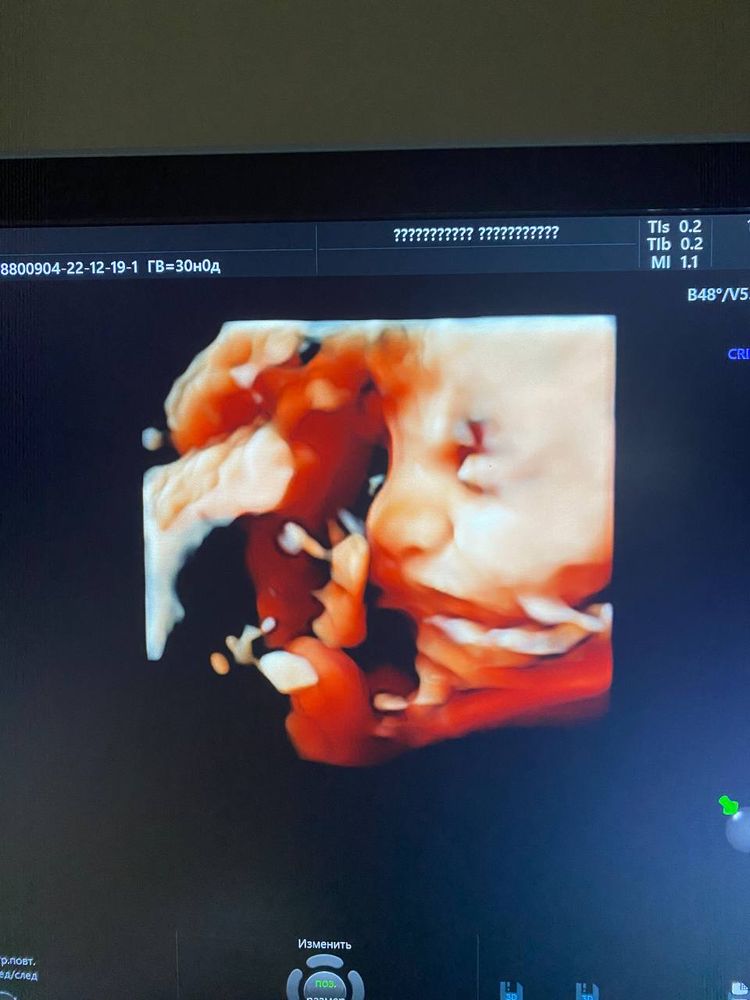

Ровно год. С последнего узи перед встречей.